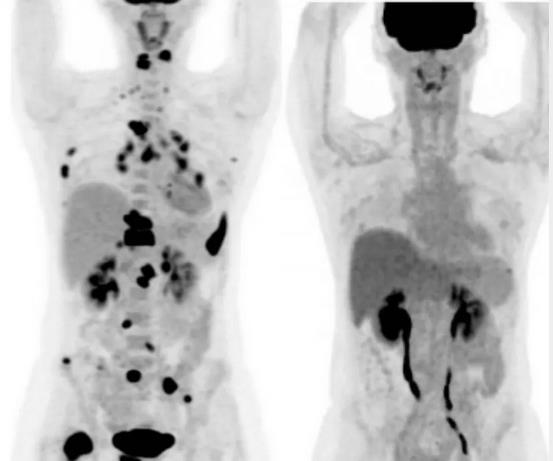

另一位35歲淋巴癌末期的臺(tái)灣男性,也是經(jīng)歷六個(gè)月的免疫細(xì)胞療法后,目前完全痊愈,全身上下已無腫瘤。

image.png